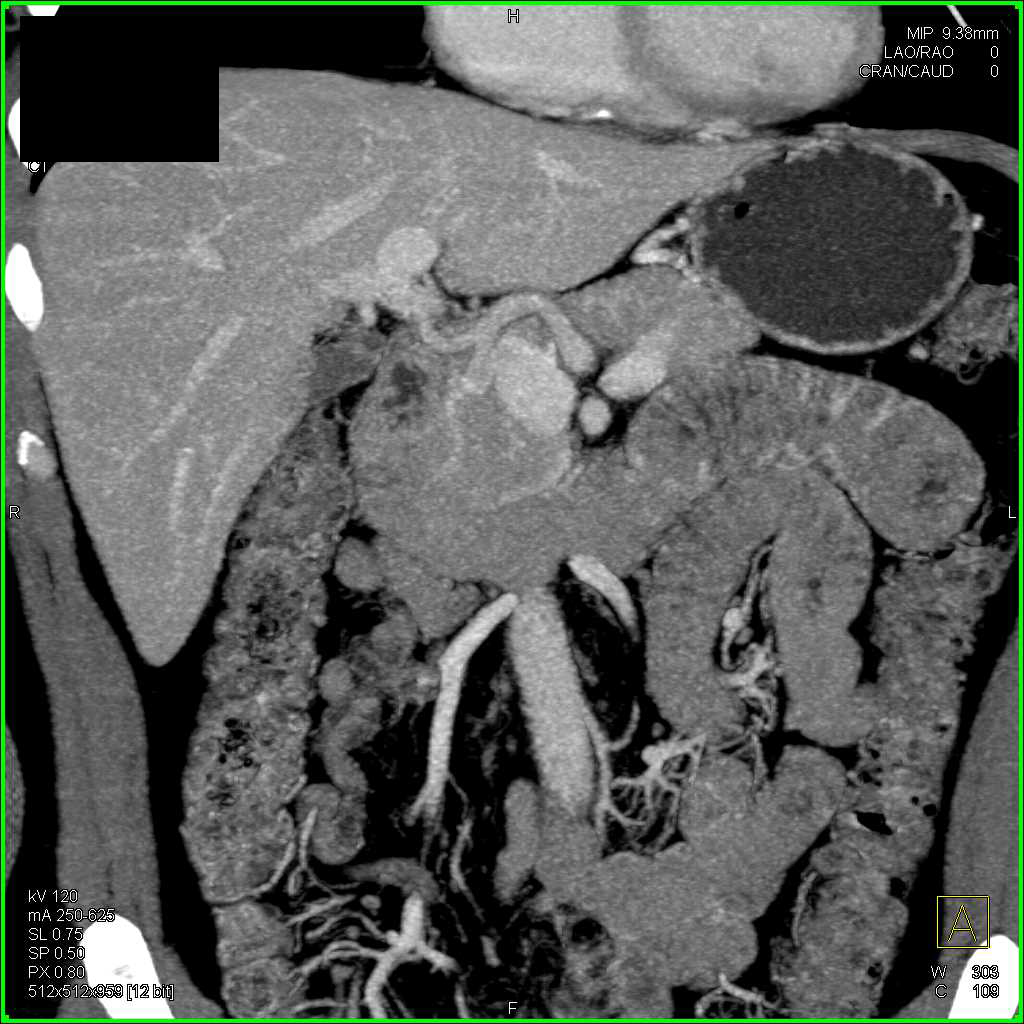

Neuroendocrine Tumor Pancreas Which is Very Vascular and Metastases to Pelvis and Bone